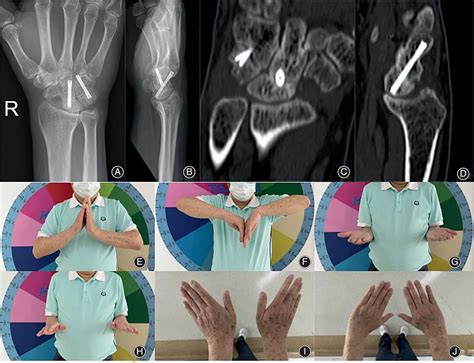

Diagnosing this condition requires a comprehensive physical examination combined with advanced imaging. Physicians typically rely on standard X-rays, which often reveal the characteristic gap in the scaphoid and the narrowing of the joint space. In more complex cases, a CT scan or MRI may be ordered to assess the exact degree of cartilage degradation and to plan potential surgical interventions.

Recovery following surgery for Scaphoid Nonunion Advanced Collapse is a marathon, not a sprint. The initial phase involves strict immobilization to allow the reconstructed joints to heal or stabilize. Once the surgeon determines that the hardware is secure or the bone has healed, physical therapy becomes the cornerstone of the recovery process.

Most patients experience a significant reduction in pain following surgical intervention. While some loss of absolute range of motion is expected, especially with fusion-based procedures, the trade-off is often a more functional and pain-free hand that allows for the return of daily activities, such as writing, cooking, and light lifting.

• scaphoid nonunion advanced collapse radiology